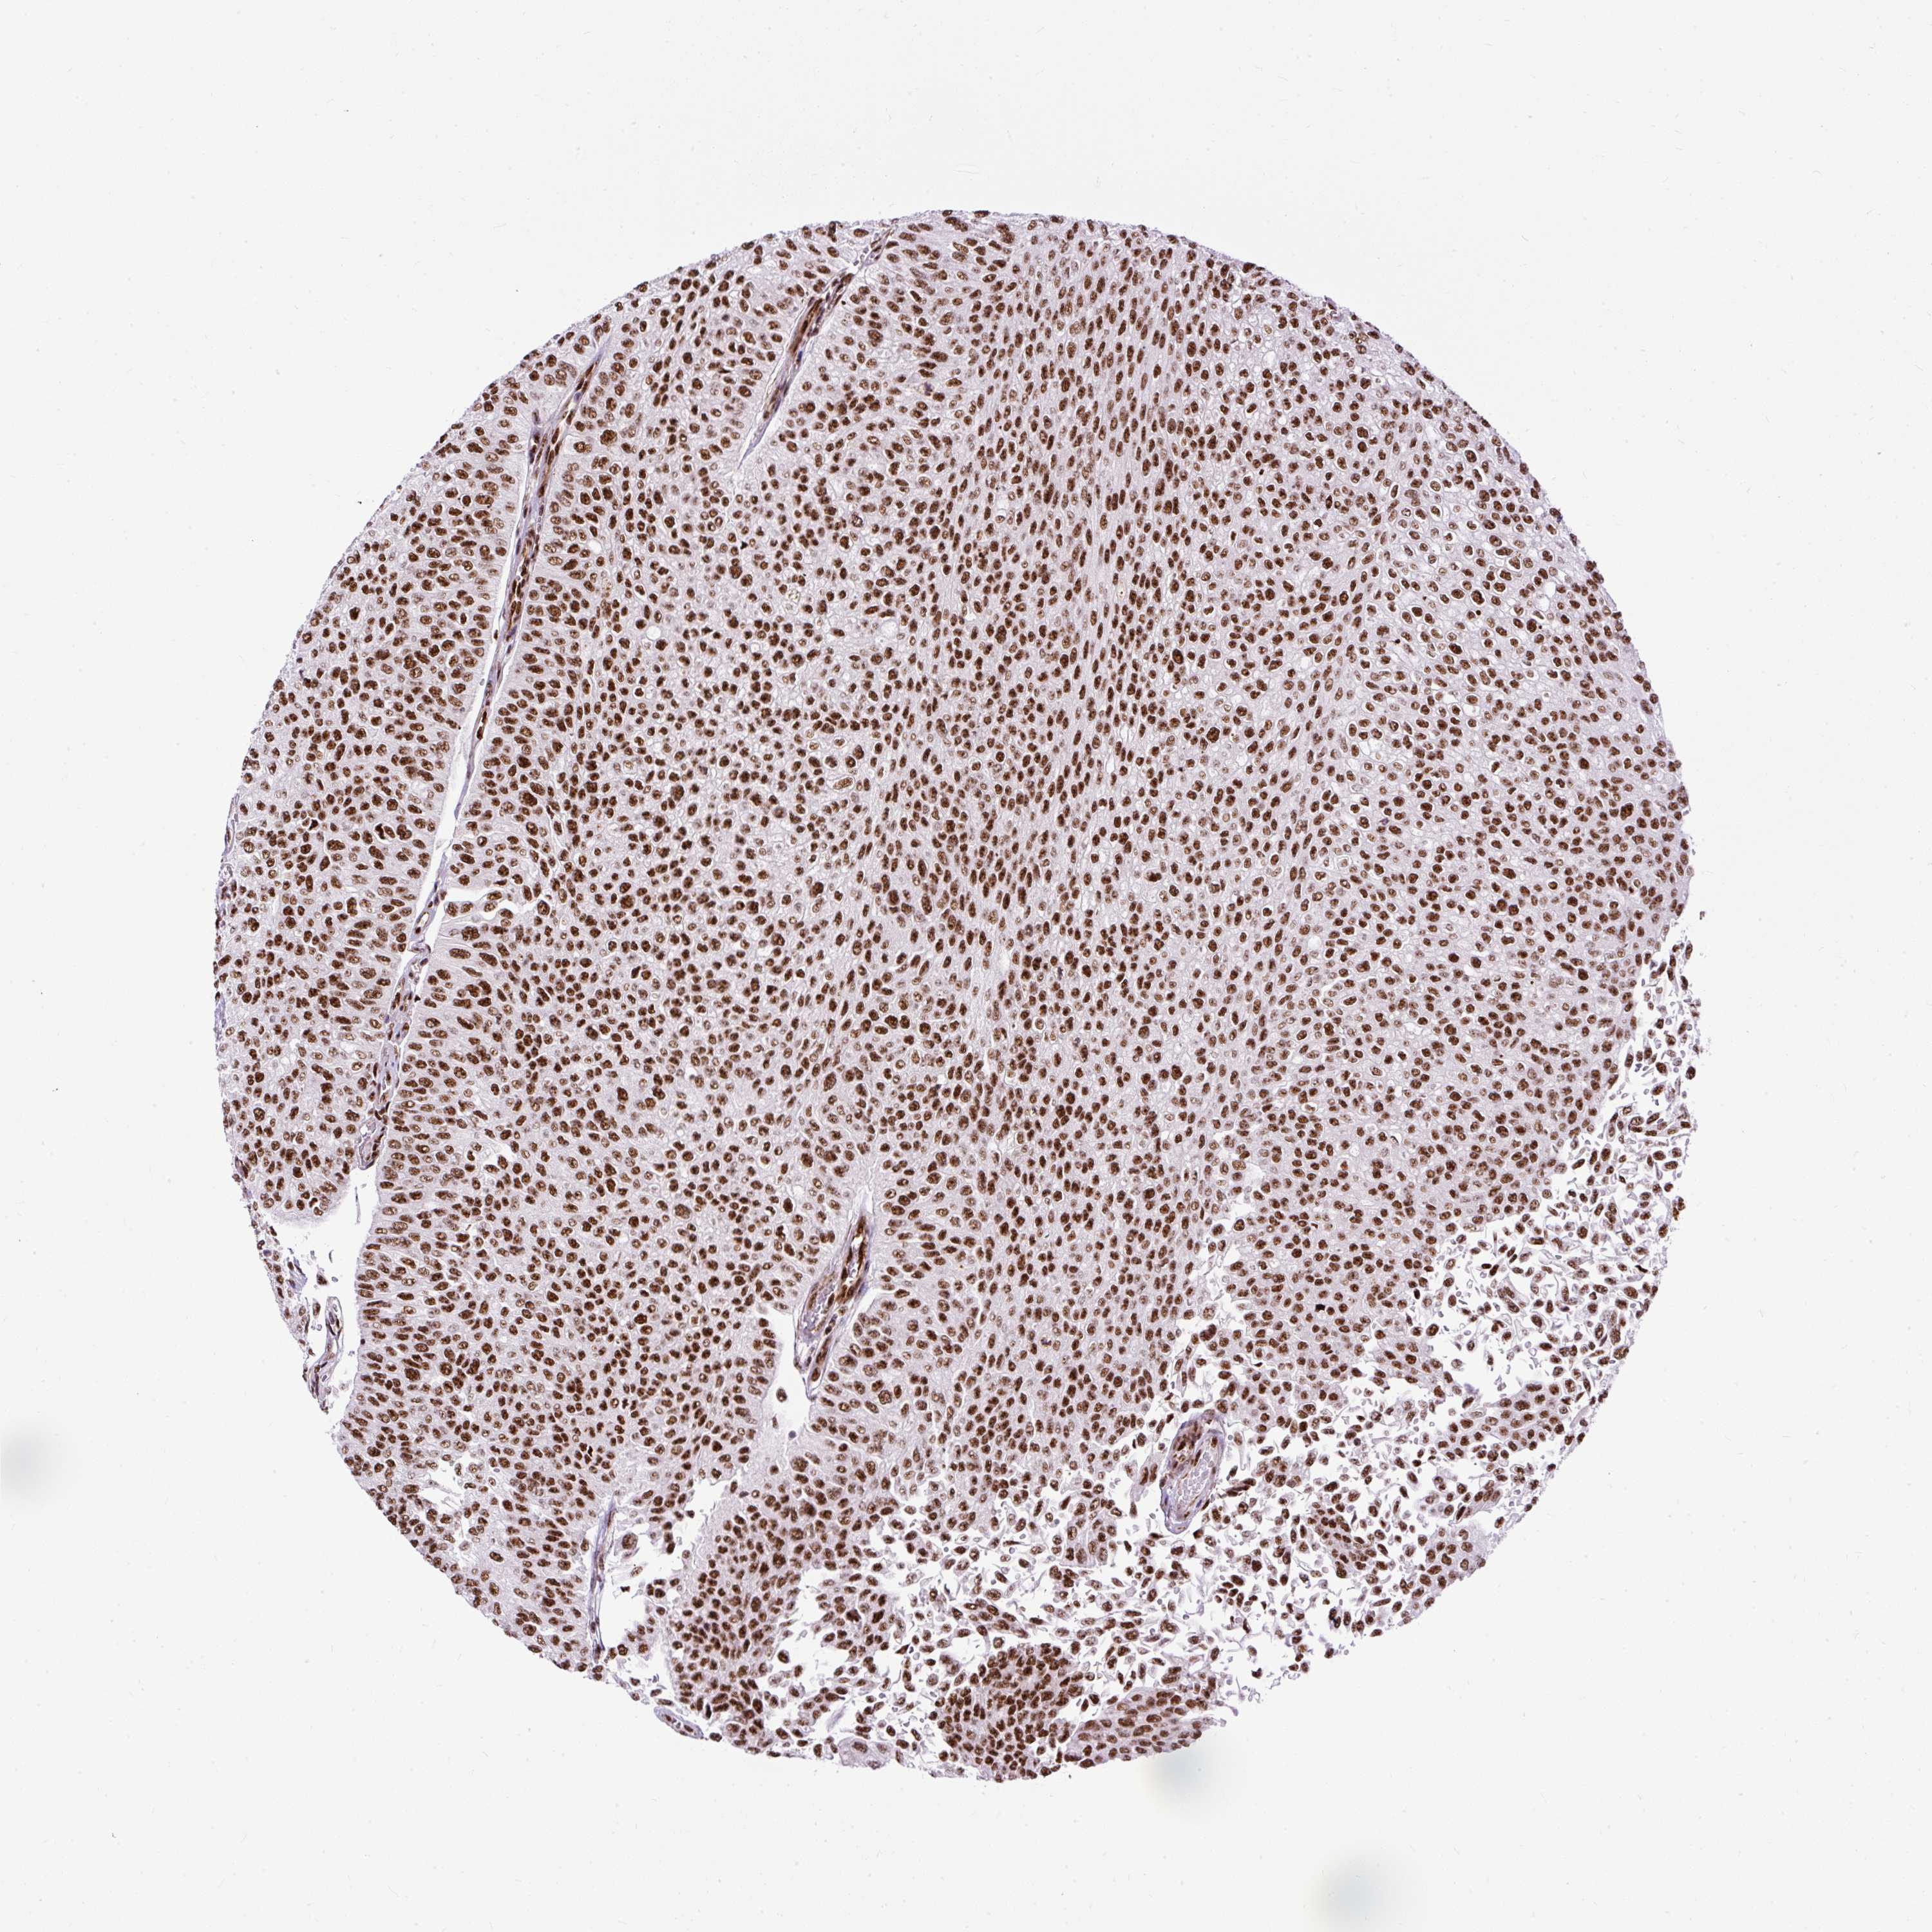

UROTHELIAL CANCER - Protein expressioni

A mouse-over function shows sample information and annotation data. Click on an image to view it in a full screen mode. Samples can be filtered based on level of antibody staining by selecting one or several of the following categories: high, medium, low and not detected. The assay and annotation is described here.

Antibody stainingi

Antibody staining in the annotated cell types in the current human tissue is reported as not detected, low, medium, or high, based on conventional immunohistochemistry profiling in selected tissues. This score is based on the combination of the staining intensity and fraction of stained cells.

Each image is clickable and will lead to virtual microscopy that enables deeper exploration of all samples and also displays staining intensity scores, fraction scores and subcellular localization as well as patient and tissue information for each sample.

Antibody HPA045663

Antibody HPA051631

Staining

High

Medium

Low

Not detected

Intensity

Strong

Moderate

Weak

Negative

Quantity

>75%

75%-25%

<25%

None

Location

Nuclear

Cytoplasmic/membranous

Cytoplasmic/membranous,nuclear

Urothelial carcinoma, High grade

Urothelial carcinoma, NOS

Urothelial carcinoma, Low grade